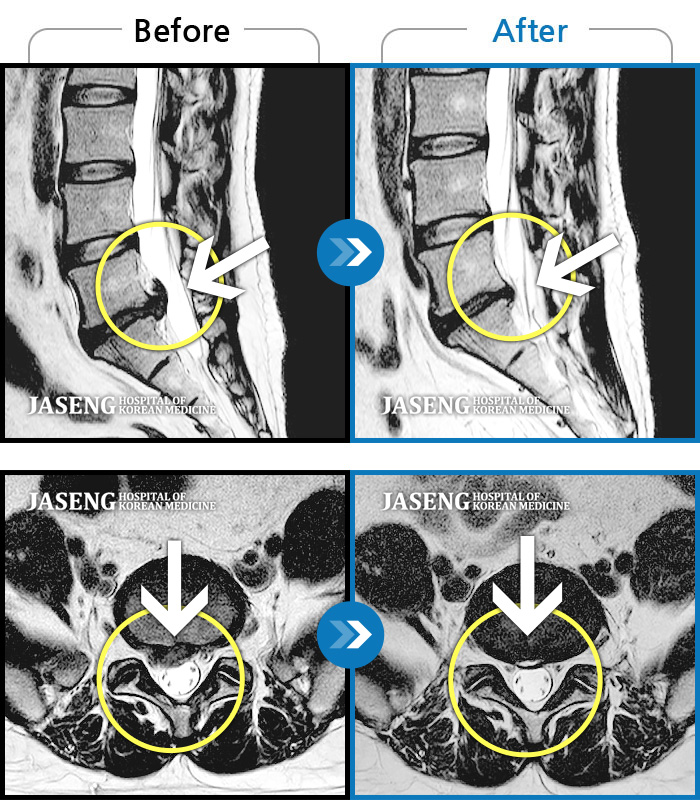

MRI 치료사례

허리와 양측 엉덩이가 아프고, 자세를 바꿀 때 통증이 더욱 심해진다.